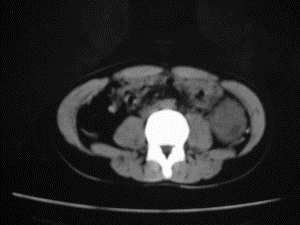

患者女,20岁,被车撞伤3小时,pe:全腹肌紧张,压痛反跳痛,以右上腹为著,肠鸣音减弱。有手术结果。![]() ![]() ![]() ![]() ![]() ![]() ![]() ![]() ![]() ![]() ![]() ![]() ![]() ![]() ![]() ![]() ![]() ![]() ![]() ![]() ![]() jiajie发言: ![]() 考虑空腔脏器穿孔。 dyqct发言:考虑:1、肝左叶外侧段断裂伤伴少量腹血。2、空腔脏器穿孔。 fangzheng发言:仅见腹腔内游离气体,提示空腔脏器穿孔。 guoke发言:胃内密度增高,肠腔内充满气体,考虑肠腔破裂出血 mmg94发言:胃后壁见一增厚软组织密度影,肝左叶前见游离气体影,左腹腔内局部肠管壁、系膜增厚。并见类圆形软组织。以上征象提示消化道管腔破裂,小肠、肠系膜挫裂伤,腹腔血肿形成。 拾荒者发言:肝实质密度不均匀,胃内见不均匀高密度影。考虑:肝挫裂伤,胃内应激性溃疡出血。 守望可可西里发言: 以下是引用jiajie在2006-6-20 15:49:00的发言:[br] [br][br]考虑空腔脏器穿孔。jiajie老师,我鼓起了很大的勇气才决定给您唱个反调儿,如果我错了,请您一定给我指出来,谢谢您了。我反复看了解剖图谱,觉得您所说的“考虑空腔脏器穿孔”上图所用箭头标明的不是游离气体。请您看以下几幅图片: ![]() ![]() ![]() ![]() ![]() ![]() ![]() ![]() 再请您看向医生老师发表的解剖图谱3幅 ![]() ![]() ![]() 这以下几幅图,我认为是肝包膜下积血。不过,说实在话,我没有发现有明显的肝挫裂伤。不对的地方请您一定指出来,再次感谢您了,jiajie 老师! ![]() ![]() ![]() ![]() 这下面几幅图片,我认为有明显的左中上腹部小肠损伤。 ![]() ![]() ![]() ![]() ![]() ![]() ![]() ![]() jiajie 老师,估计我说的是错误的,但我实在闹不明白,请您一定不要笑话我,并指出我的错误,以便于我减少工作中的失误。再次感谢您了,jiajie 老师! 至于胃内的不均匀高密度,我认为拾荒者战友说的有道理,胃内应激性溃疡出血和胃内容物混合所致。 手术结果:左肝叶(iv段)前缘长约8cm挫裂伤口,舌叶根部下< |